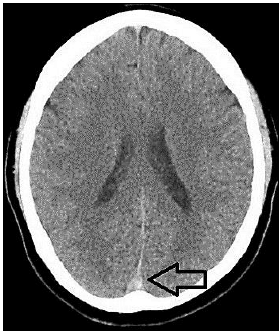

“Paciente, sexo feminino, 40 anos de idade, tabagista ativa, teve quadro de Covid-19 leve há uma semana, evoluindo com cefaleia holocraniana persistente, de forte intensidade, refratária à analgesia simples. Nega ter cefaleia prévia. Após três dias de dor, cursou com um episódio de crise convulsiva generalizada, sendo, então, levada ao hospital de referência próximo a sua residência, onde realizou a seguinte tomografia computadorizada de crânio sem contraste:”

De acordo com as informações, a indicação na tomografia computadorizada de crânio sem contraste se refere ao seguinte sinal radiológico:

Considerando o caso hipotético, qual o diagnóstico da paciente?